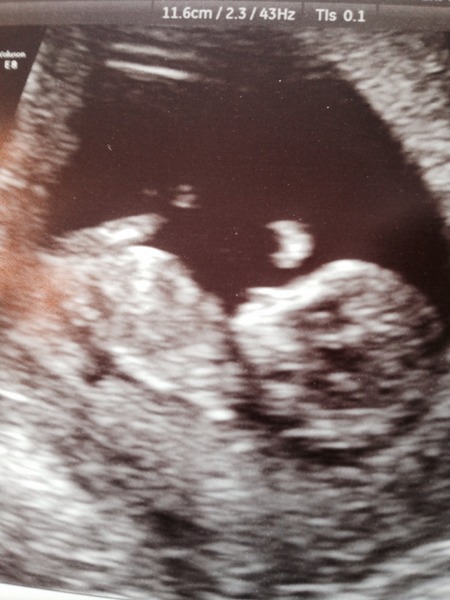

Azquilith · 23/06/2015 19:40

A little wave from my 11+5 baby to you all.